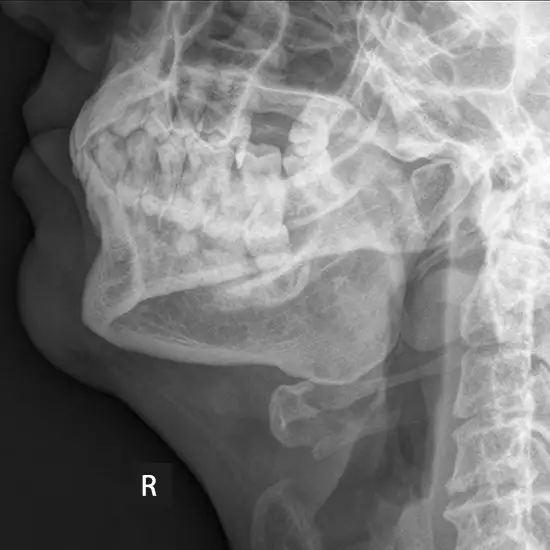

X-Ray Mandible Right Lateral Oblique View

An X-ray of the mandible (jaw) visualizes the jaw bone, TM joint (temporomandibular joint), and surrounding soft tissues such as muscles.